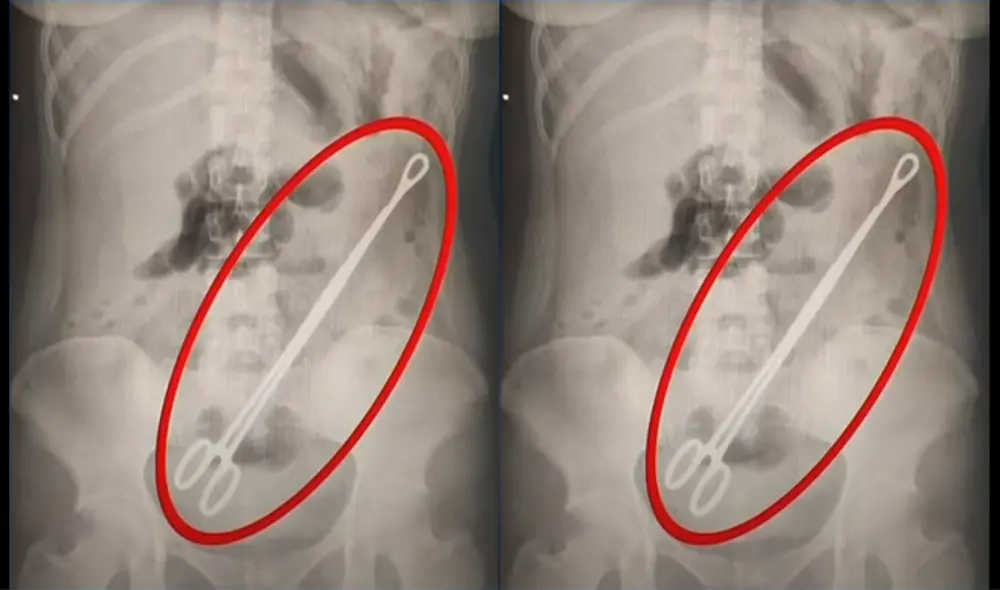

La joven fue operada tras permanecer con el instrumento por más de seis meses en su interior. El objeto quirúrgico medía aproximadamente 20 centímetros.

Lesly Cagua, una joven madre de 20 años, tuvo a su hijo a mediados de marzo en el hospital Delfina Torres, ubicado en la ciudad de Esmeraldas. La víctima denunció, a través del canal local Ecuavisa, que los médicos olvidaron una pinza de aproximadamente 20 centímetros dentro de su cuerpo.